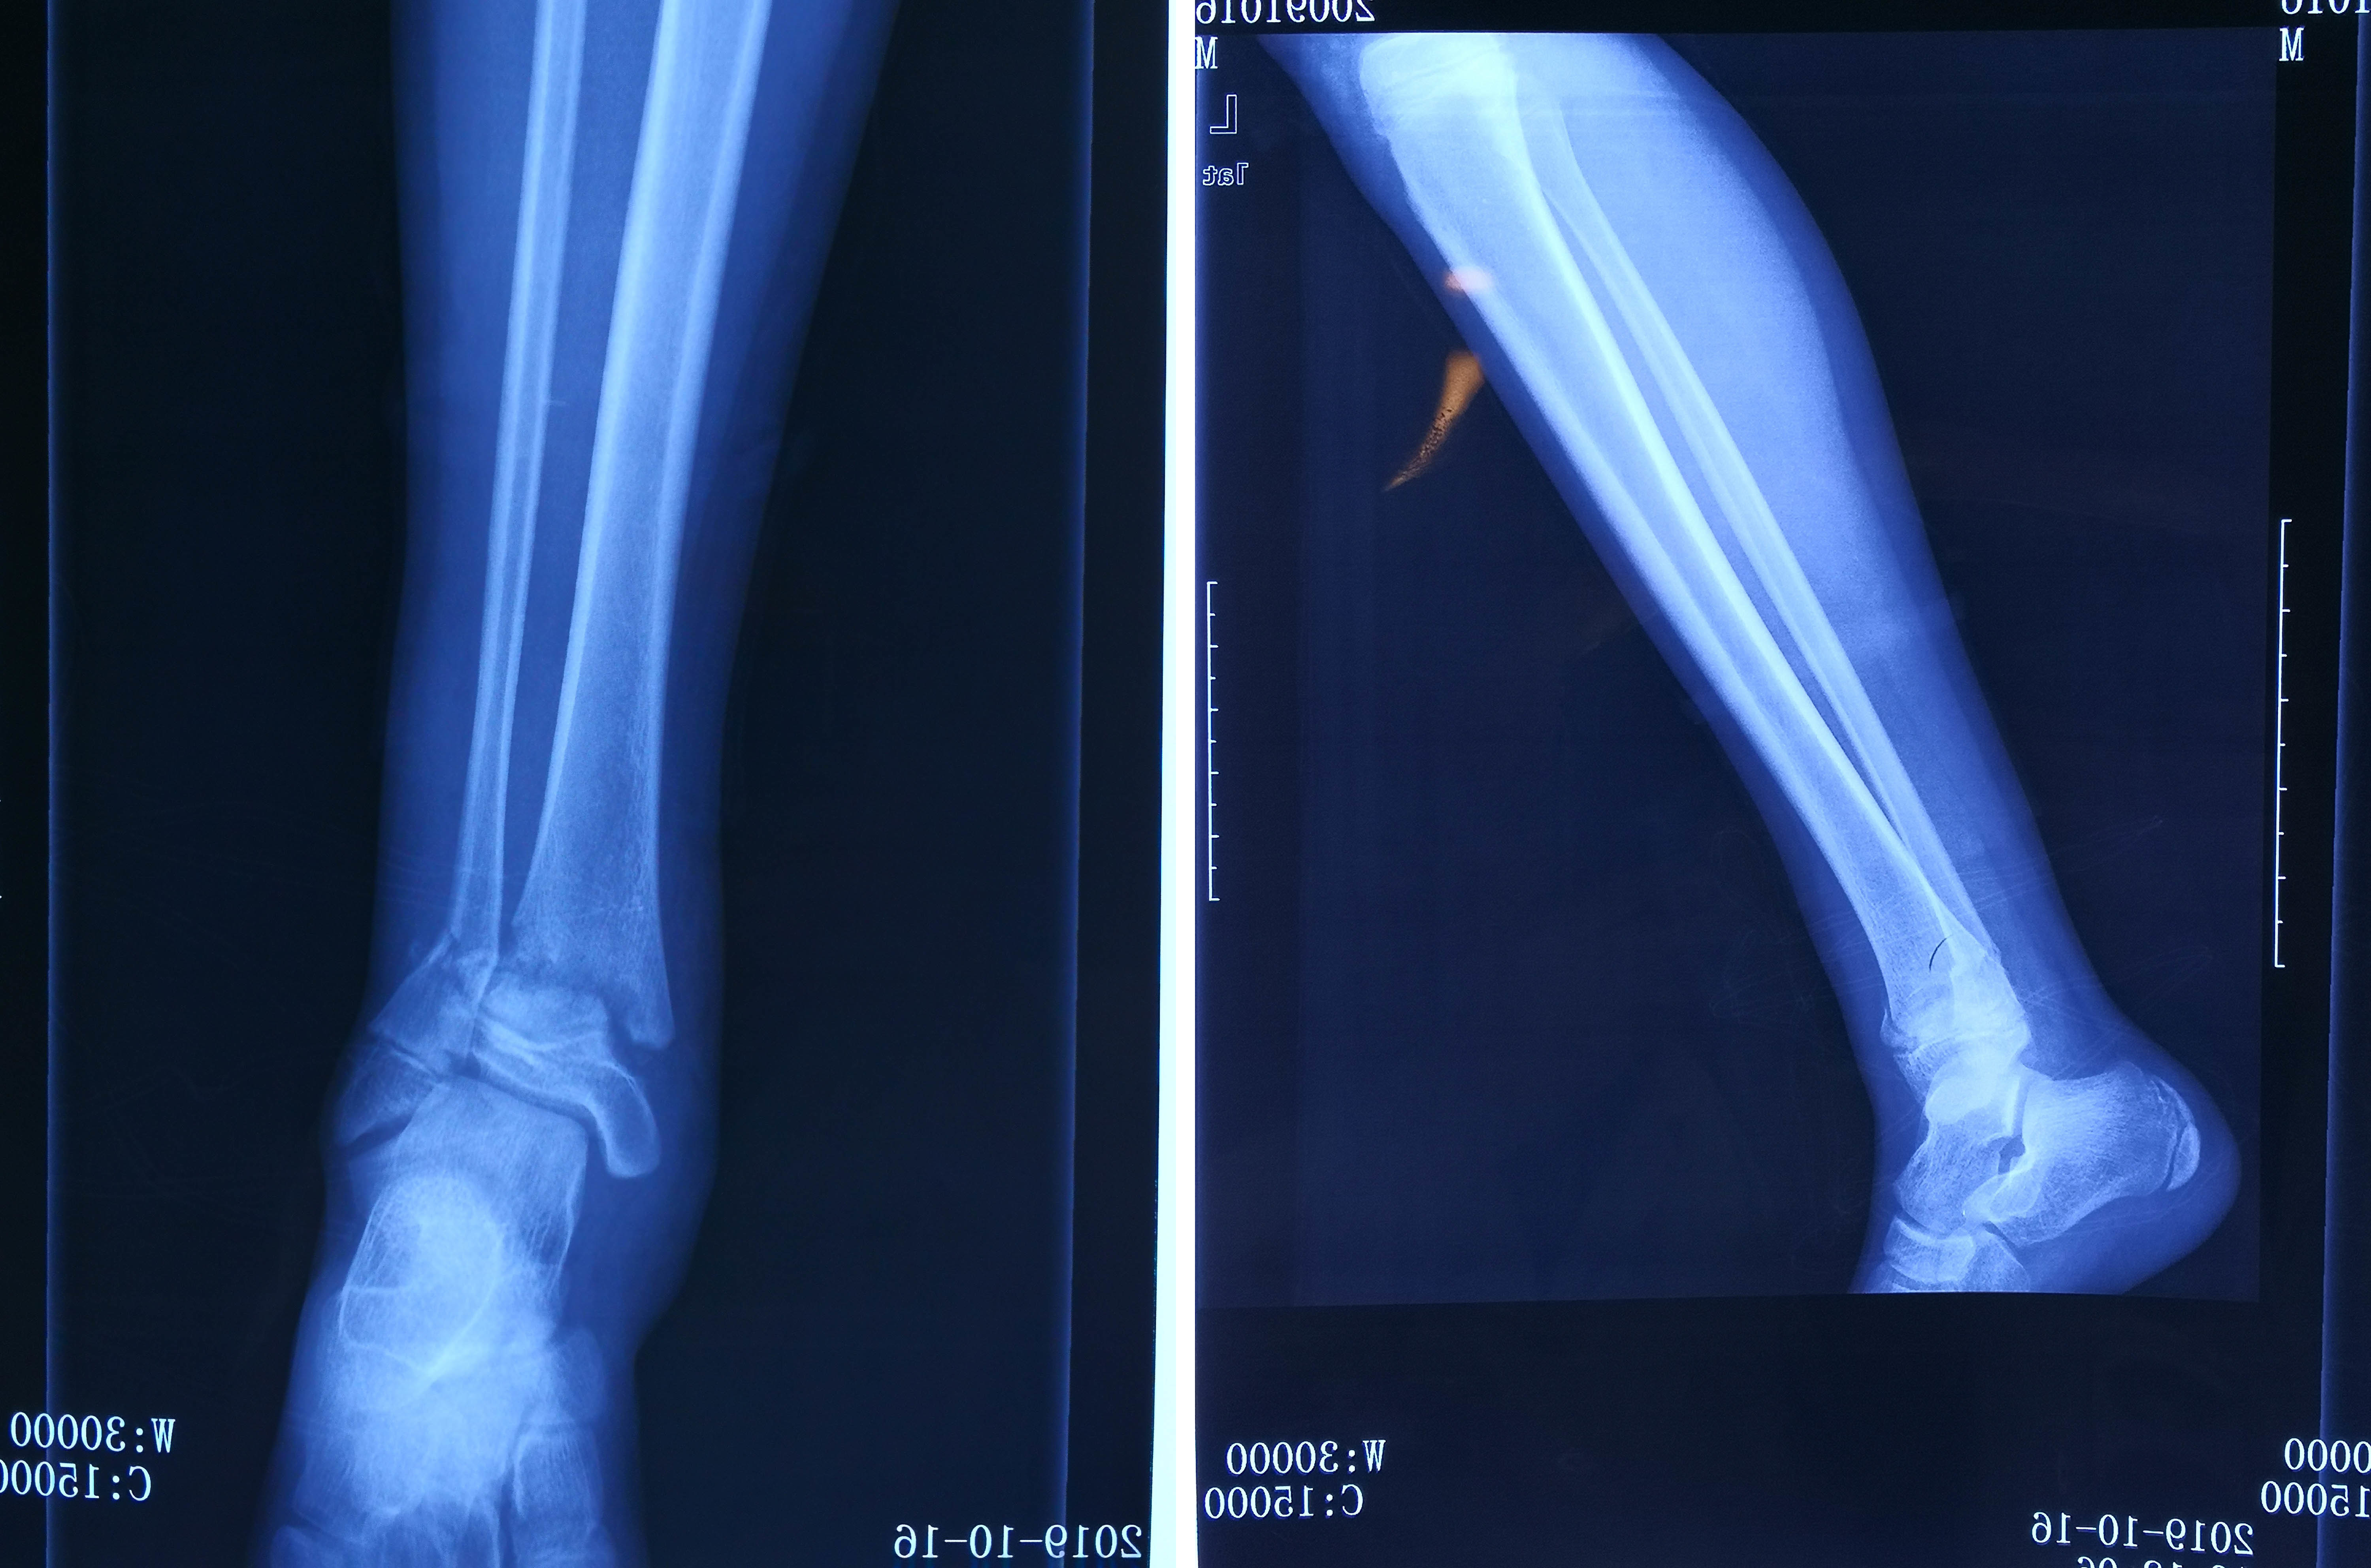

POINT 下腿骨骨折(脛骨骨折、腓骨骨折)とは すねの骨は脛骨と腓骨の2本からなりますが、下腿骨骨折はそのうち一方または両方が骨折することで、交通事故やスポーツ、転倒が原因で起こることが多いです。 骨折した部分は腫れや痛み、内出血がみられます。 レントゲン検査やCT検査などの画像検査によって骨折の部位や程度が調べられます。 骨折の程度によっAO/OTA分類 続いて、もう少し詳しい分類についてまとめていきます。 AO/OTA分類 は、骨盤後方部の損傷程度(部分破綻・完全破綻)から骨盤輪の安定性により分類しています。 Pannal分類では、骨折を生じる際に加わった外力の方向を、前後方向の圧迫(anteroposterior compression)、側方からの圧迫今回は脛骨高原骨折について、 まるごと理解してしまおう! ということで、専門医の視点を 少しでもわかりやすく、噛み砕いて 解説いたします。 こんにちは、スポーツ整形外科医の歌島です。 本

すねの骨を骨折することを、 脛骨高原骨折(けいこつこうげんこっせつ) 脛骨近位端骨折(けいこつきんいたんこっせつ) 脛骨プラトー骨折 このように表現されることが多いのですが、どれも同じ骨折になります。以下①~③を調べた上で骨折を分類。AO分類がよく使われる。 ①骨折型は? ②骨折の範囲は? ③転移の方向とその程度は? AO分類 開放骨折の場合は更に分類が必要。Gustilo分類が良く利用されている。 Gustilo分類 治療 ①横止め髄内釘法 適応:脛骨中央の骨折外側ヒンジ骨折(LHF) LHFの 正確な評価が重要 Takeuchi分類 TypeⅠは安定 • 開大部癒合遷延 TypeⅡ/Ⅲは不安定 • 矯正損失の可能性 内側開大式高位脛骨骨切り術(OWHTO) の予後を左右する重要な合併症